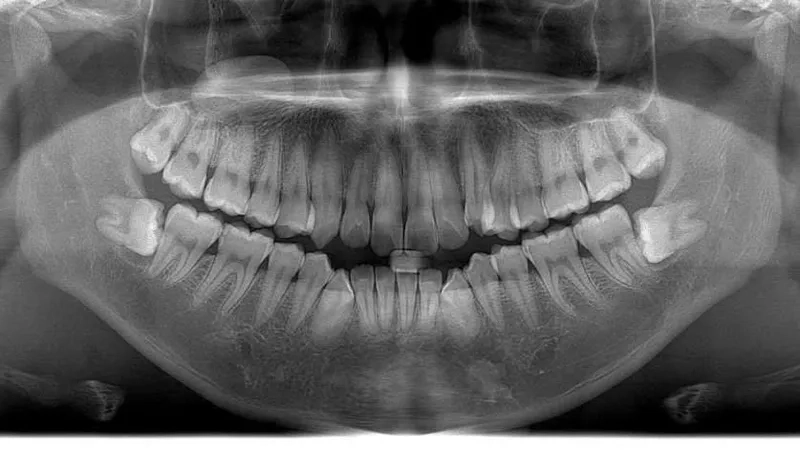

Chính vì là kẻ đến sau cùng, răng khôn thường không tìm được vị trí thuận lợi để mọc thẳng. Chúng phải tìm cách chen chúc, dẫn đến các tình trạng phổ biến như mọc lệch, mọc ngầm dưới nướu hoặc đâm ngang vào chiếc răng số 7 bên cạnh.

Hủy hoại cấu trúc răng số 7 lân cận

Khi răng khôn mọc lệch hoặc đâm ngang, nó sẽ trực tiếp húc vào chân răng số 7. Lực đẩy này diễn ra âm thầm nhưng mạnh mẽ, làm tiêu chân răng, gây sâu răng số 7 và có thể khiến chiếc răng này bị lung lay hoặc mất vĩnh viễn.

Nguy cơ hình thành u nang xương hàm

Trong một số trường hợp răng khôn mọc ngầm hoàn toàn trong xương, các mô bao quanh răng có thể phát triển thành u nang.

Nếu không được phát hiện qua phim chụp X-quang, u nang này sẽ âm thầm phá hủy xương hàm, làm tổn thương các dây thần kinh và các răng xung quanh, gây ra những tổn thương nặng nề khó phục hồi.